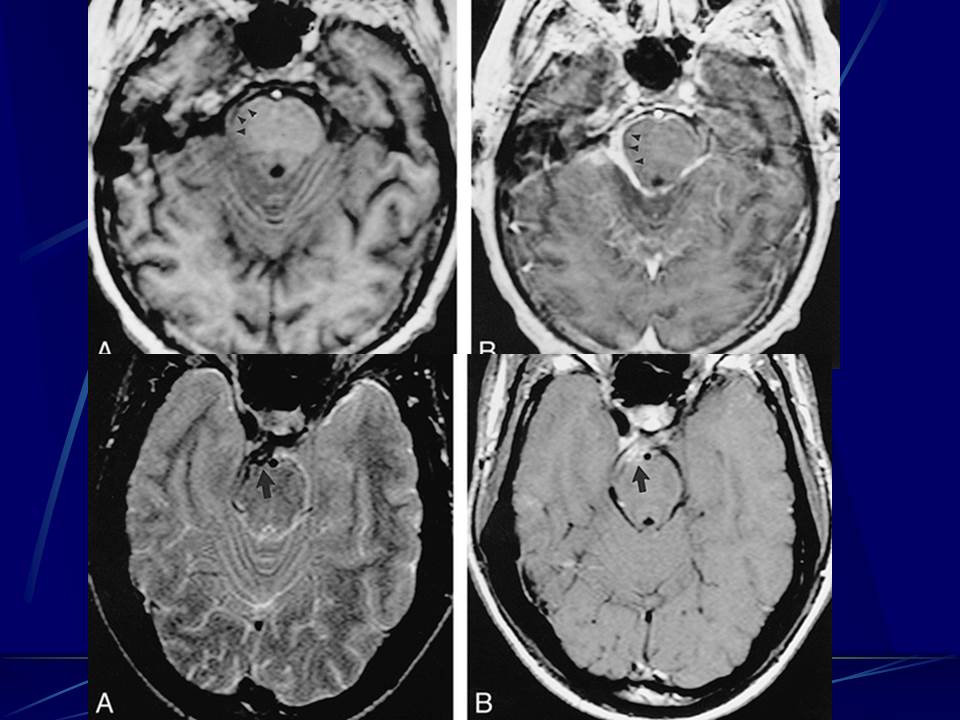

肺部真菌感染影像学分析